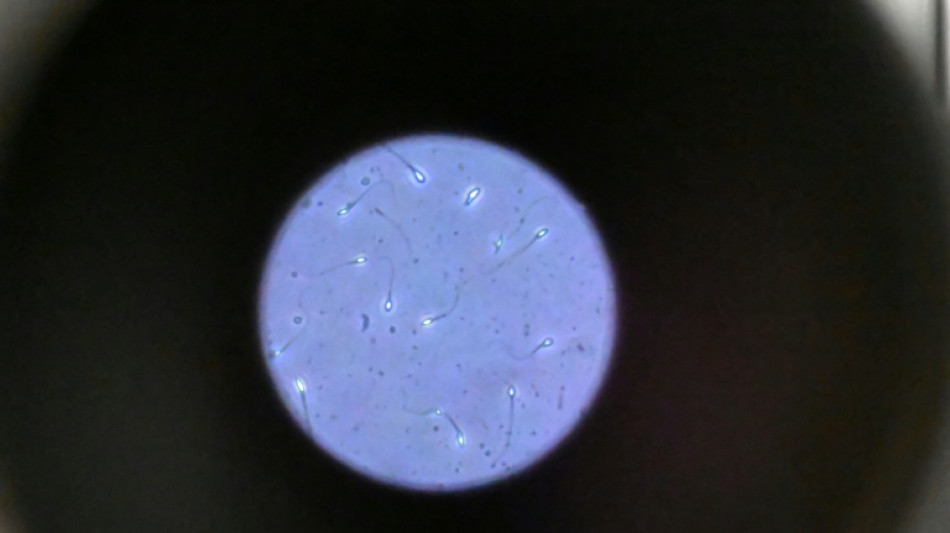

Dans l'espace, les spermatozoïdes ont du mal à trouver leur chemin

Dans l'espace, les spermatozoïdes ont du mal à trouver leur chemin vers l'ovule en raison de la microgravité, qui perturbe aussi le développement des embryons, selon une étude publiée jeudi dans Communications Biology.

"Les spermatozoïdes doivent activement trouver leur chemin vers l'ovule et cette étude est la première à tester leur capacité à le faire dans des conditions semblables à ce qui se passe dans l'espace", explique à l'AFP Nicole McPherson, autrice principale de l'étude et chercheuse à l'Université d'Adelaïde (Australie).

Son équipe a utilisé une chambre en plastique imitant l'appareil génital féminin, qui leur a servi de "parcours d'obstacles miniature". "Voyez ça comme un minuscule circuit de course... Les spermatozoïdes étaient introduits à une extrémité et devaient nager jusqu'à l'autre bout", décrit-elle.

Les chercheurs ont testé successivement du sperme de souris et humain dans ce dispositif placé dans un appareil en constante rotation pour simuler la microgravité.

Les gamètes ont été environ 50 % moins performants pour naviguer à travers ce parcours que sous la gravité terrestre. Cela équivaut à une baisse de 30% du taux de fécondation réussie, selon les résultats de l'étude.